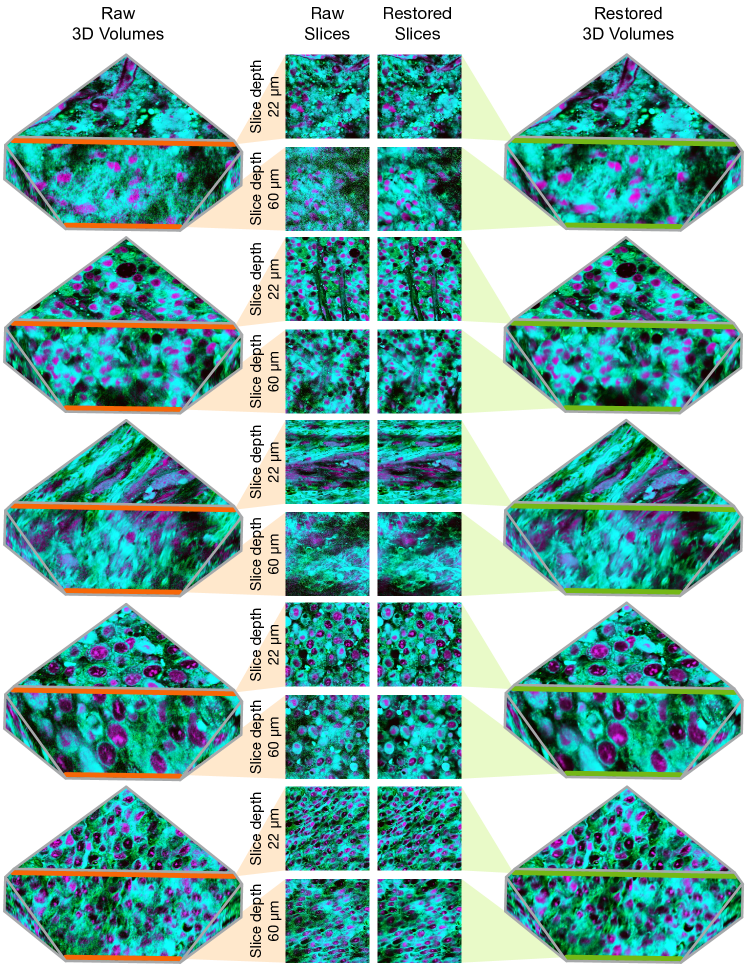

Refer to caption

Figure 8: Depth z-stack restoration results. The raw 3D z-stack volume (left) and the restored volume (right) are shown. Depth z-images in the center show image restoration using RSCD. The top and bottom plots show the pixel intensities along the row indicated in orange and green in the adjacent images. As depth increases from 22 microns to 60 microns, image noise increases as shown in the orange, low-quality pixel intensities. However, images restored by RSCD show little to no additional noise with increasing depth.

RSCD was used to restore z-stacked SRH images taken from 425 surgical specimens. Additional information regarding the dataset can be found in Appendix 0.E.2. FID scores were computed at each z-depth level for original and restored images with respect to the 4.5K high-quality SRH images. We show the results in Figure 9. FID scores for the original low-quality images steadily increase as imaging depth increases, indicating worse image quality with imaging depth. RSCD consistently reduces the FID score for deep SRH images, cumulatively improving the overall quality of the z-stacked volume, shown in Figure 8.

We include additional examples of restored z-stack images spanning a variety of tumor types in Figure 16.

Figure 16: Additional depth z-stack restoration results. The raw 3D z-stack volumes are shown on the left and the restored volumes using RSCD are shown on the right. The center images are the cross-section views of the first and the last slices, at 22 and 60 microns, respectively. Image noise increases as the tissue depth increases due to tissue scattering. With RSCD, the restored images show little to no additional noise in deep images.